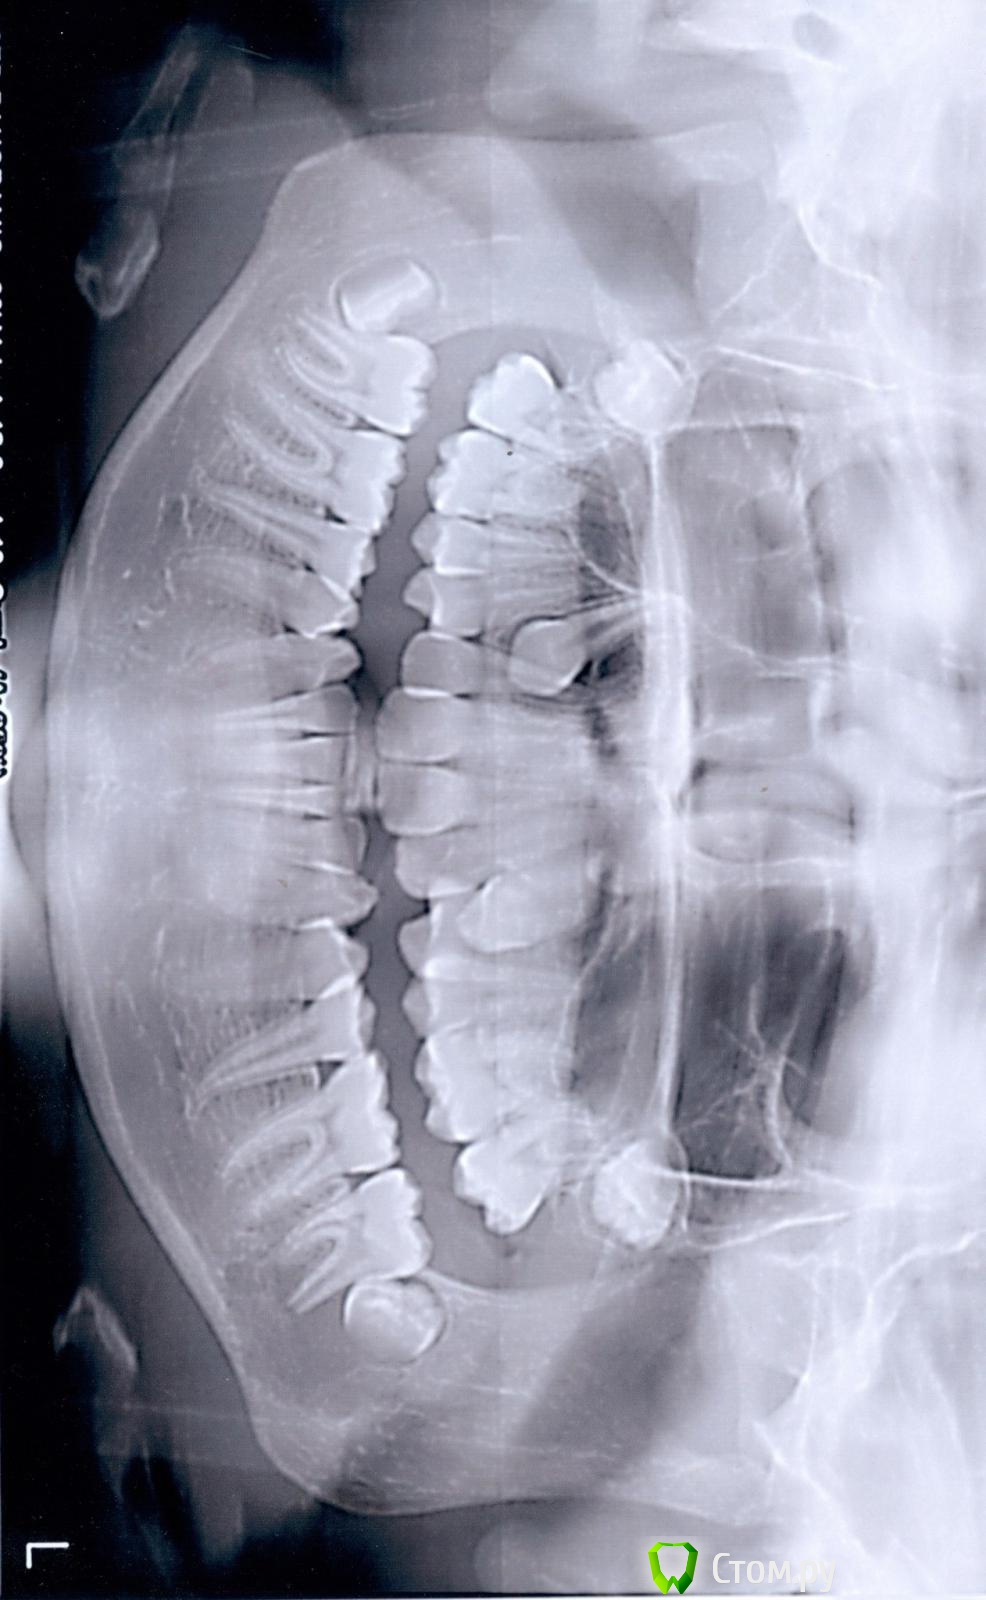

Элько Опубликовано 21 августа, 2014 Поделиться Опубликовано 21 августа, 2014 Здравствуйте! Девочка 12.5 лет . Доктор, сделав панорамный снимок, дала направление на удаление 24 зуба и через два месяца на прием с дальнейшим удалением с другой стороны . Так как клыкам нет места совсем на челюсти они лезут сверху вторым рядом. над 24 уже прорезался а с другой стороны еще нет. Подскажите удаление здоровых коренных зубов как в дальнейшей жизни скажется? И возможны ли другие варианты лечения. Ссылка на комментарий

Ayrat_zub Опубликовано 21 августа, 2014 Поделиться Опубликовано 21 августа, 2014 Здравствуйте! Девочка 12.5 лет . Доктор, сделав панорамный снимок, дала направление на удаление 24 зуба и через два месяца на прием с дальнейшим удалением с другой стороны . Так как клыкам нет места совсем на челюсти они лезут сверху вторым рядом. над 24 уже прорезался а с другой стороны еще нет. Подскажите удаление здоровых коренных зубов как в дальнейшей жизни скажется? И возможны ли другие варианты лечения.упражнение для шеи решили устроить?)) снмики первернутые как попало) можно буз удаения 4-ок, еще одного снимка не хватает Ссылка на комментарий

Ayrat_zub Опубликовано 22 августа, 2014 Поделиться Опубликовано 22 августа, 2014 Я не знаю почему они в разные стороны у меня все ровно было а выгрузилось так .А какой еще нужен снимок? и как без удаления ? Я так понимаю с удалением проще все поставить на место, но как это аукнется в дальнейшем? снимок ТРГ, и кт в области верхних клыков, удалить скорее всего рпидется, но не 4-ки, а зубы мудрости, хотя на верхней челсюти есть варианты) сделайте более четкие фото) по поводу ортодорнта-http://forum.stom.ru/topic/4747-posovetuite-ortodonta-v-gorode-n/ Ссылка на комментарий